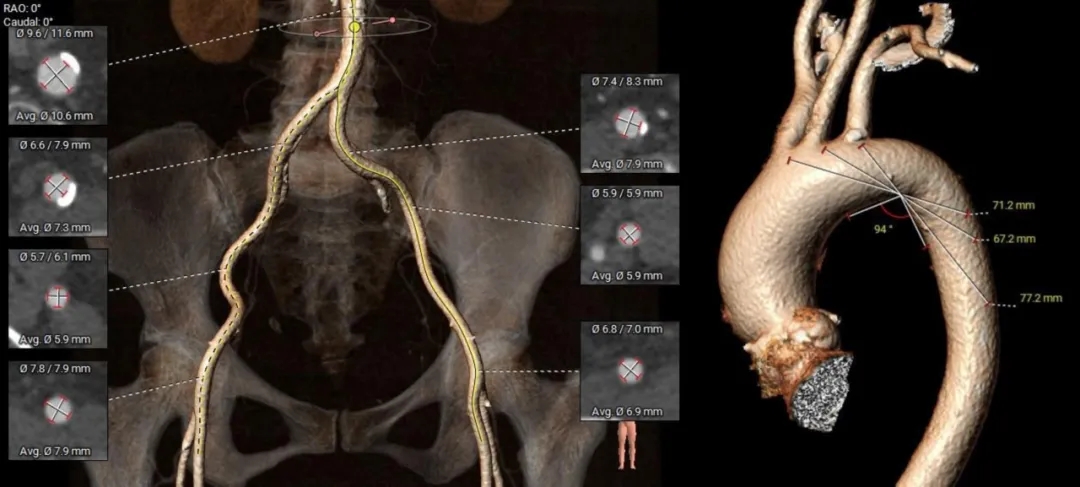

手术策略制定

此为3例中年龄最大的患者,经术前评估其高龄+Type1型二叶瓣+极重度钙化+不对称分布的特征,TAVR手术操作难度与风险显著升高。为使瓣膜安全精准释放,植入后有效撑开钙化限制,充分展开获得较好的成形,考虑选用国产创新瓣膜ScienCrown系统植入,充分利用其优势设计(直筒型瓣架提供充足的平衡支撑力、100%全释放与全可回收功能确保瓣膜安全精准植入)为TAVR手术保驾护航,为患者带来更优的获益。

-

麻醉方式:全身麻醉

入路选择:右侧股动脉为主入路

球囊扩张策略:20mm球囊

植入瓣膜型号:ScienCrown TAVTF 25

术中影像

根部造影

瓣叶活动差,可见明显反流,猪尾导管测量跨瓣压差约50mmHg

20mm球囊预扩

微腰微漏,左右冠均显影

造影确认瓣环与瓣膜位置

瓣膜0位初始定位释放,展开过程微微下移

全展开位造影评估

瓣膜呈直筒型,微腰,大弯侧约瓣下3mm,少量反流,冠脉显影

瓣膜无张力脱钩

植入后造影评估

瓣膜位置合适,可见少量反流

多角度造影评估

瓣膜形态可,冠脉显影,猪尾测量压差为0

术前术后超声对比

20260112→20260124

峰值流速:4.6m/s→2.1m/s